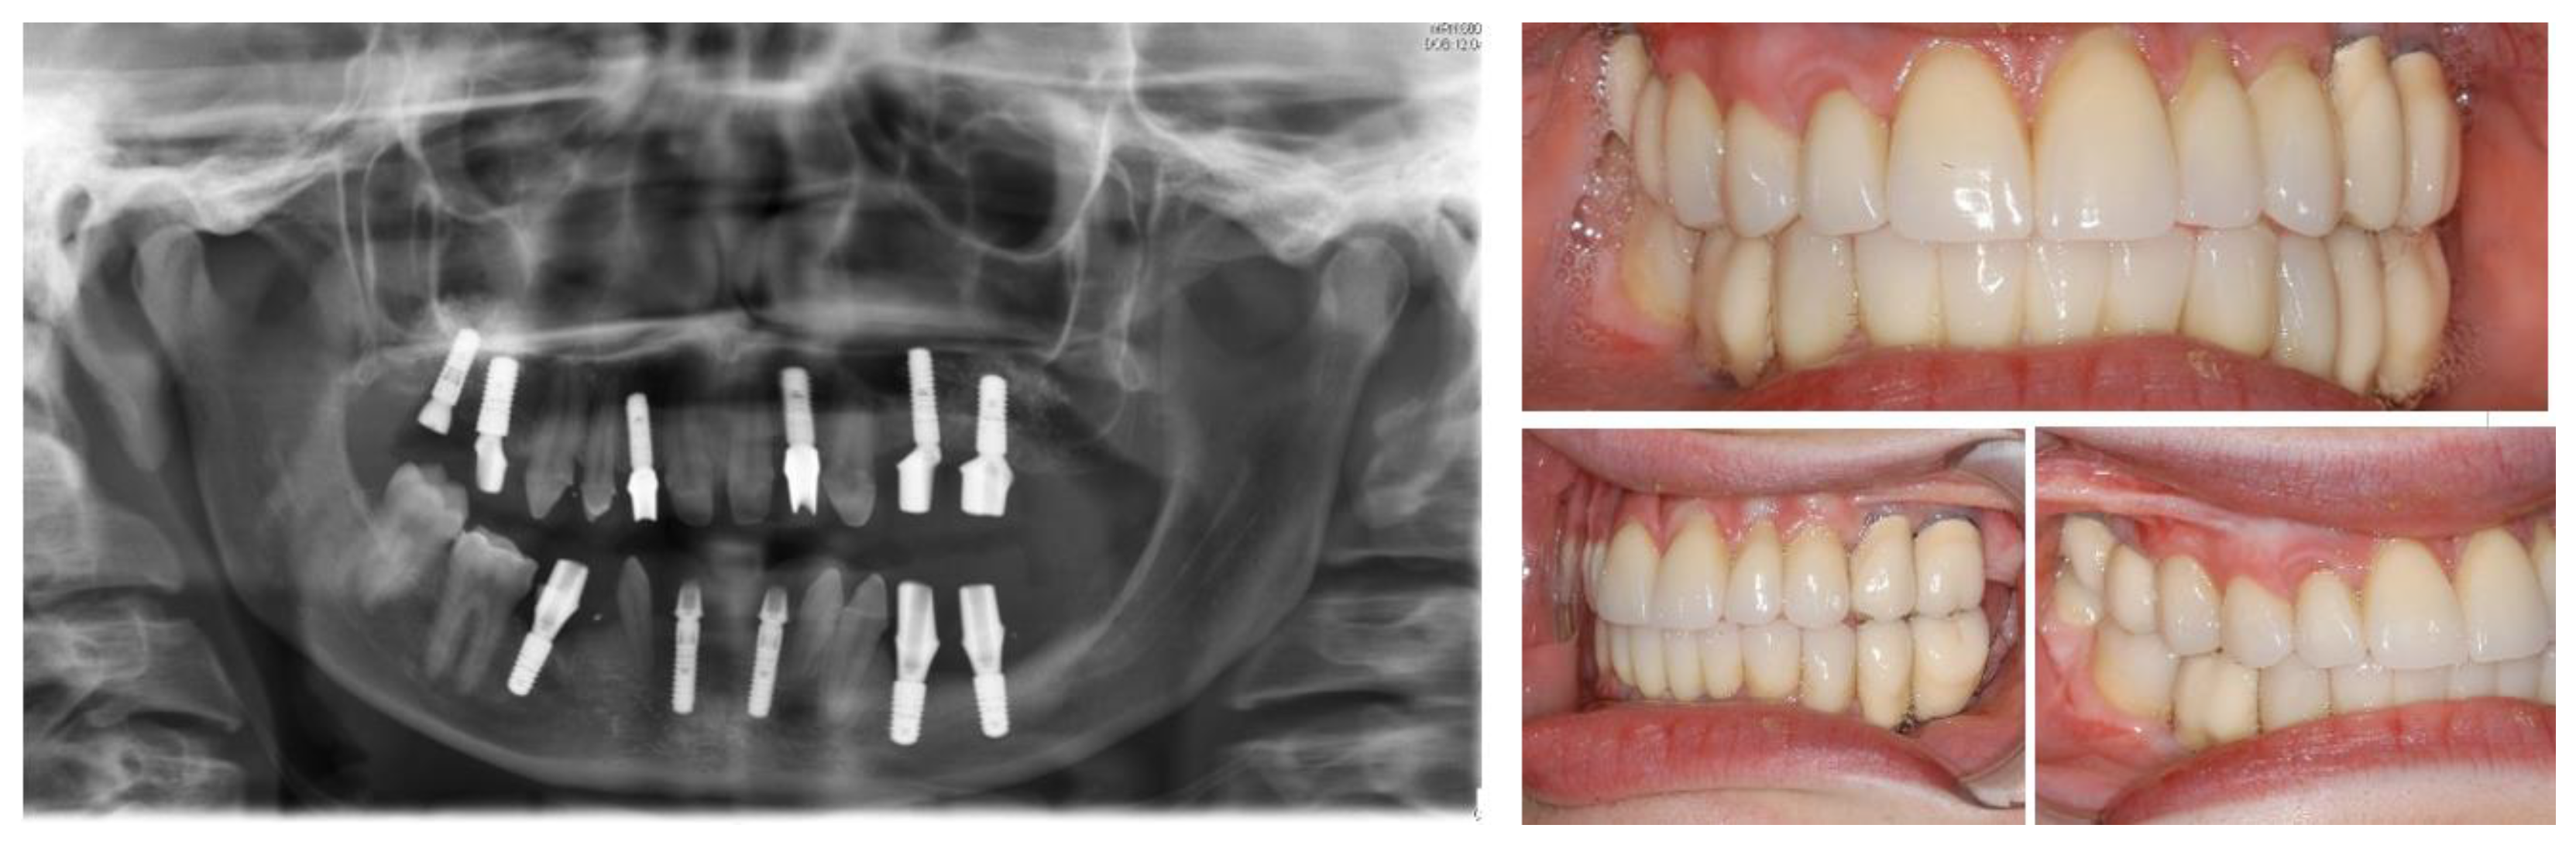

Figure 5.

Left: final orthopantomogram showing the dental implants. Right: intra-oral situation after final rehabilitation with dental-supported and implant-supported prosthesis [12].

Figure 10.

Post-operative panoramic radiography.

Figure 11.

Definitive rehabilitation with dental-implant supported prosthesis.

Titanium dental implants (Bone Level, 3.33 × 12 mm and 4.1 × 8–10 mm, Straumann, Basel, Switzerland) were placed under local anesthesia (Septanest 1:200,000) at sites 13, 23, 36, 45, 46, using the surgical guide as reference. After a healing period of three months, implant-supported porcelain crowns were installed with a torque strength of 35 Ncm. Additionally, teeth 13 and 23 were prepared for a crown with shape of premolar teeth, and porcelain crowns were cemented using resin cement (RelyX, 3M, Neuss, Germany). The treatment showed satisfactory aesthetic and functional results at 1-year follow-up. Dental implants were osseo-integrated without marginal bone loss (Figure 10 and Figure 11).